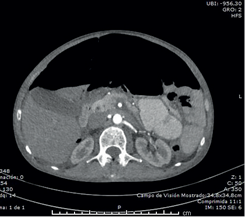

En los exámenes de laboratorio se encontró función renal y hepática normales, no había leucocitosis ni neutrofilia, la albúmina sérica fue de 3,5 g/dl y el VIH fue negativo. En las radiografías de tórax y de abdomen en posición vertical, se observó una gran cámara de neumoperitoneo que desplazaba el hígado y el bazo hacia abajo.

Al no encontrarse signos de irritación peritoneal, se practicó una tomografía toraco-abdominal en la que se observó: derrame pleural bilateral con engrosamiento de las cisuras, bronquiectasias basales bilaterales, atelectasia parcial de ambos lóbulos inferiores, notoria distensión del esófago con sonda en su interior, hidroneumoperitoneo, abundante líquido libre en la cavidad abdominal y distensión de las asas intestinales (figuras 1,2,3).